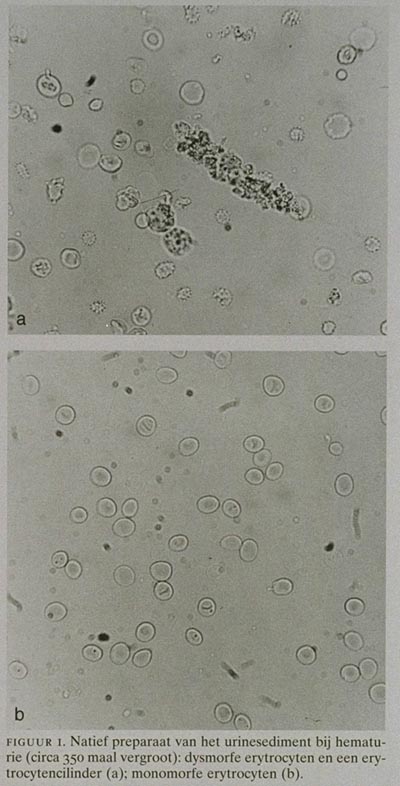

Dysmorfe erytrocyten in het urinesediment bij het onderscheiden van urologische en nefrologische oorzaken van hematurie

Vaststellen of het bepalen van dysmorfe erytrocyten in het urinesediment kan helpen bij het onderscheid tussen urologische en nefrologische oorzaken van hematurie.

Bij een grenswaarde van 40 dysmorfie was de sensitiviteit voor een urologische aandoening 100 en de specificiteit 66,7. Als naast 40 of meer dysmorfie van de erytrocyten ook de aanwezigheid van erytrocytencilinders, hemoglobinecilinders of vetcilinders als criterium voor een nefrologische oorzaak werd gebruikt, steeg de specificiteit tot 88,1. De tellingen van dysmorfe erytrocyten door twee onderzoekers toonden een correlatiecoëfficiënt van 0,90 (kappa: 0,77).

De morfologische beoordeling van de erytrocyten in het urinesediment is een betrouwbaar hulpmiddel bij het bepalen van het te volgen beleid bij hematurie. Voorwaarde is echter dat strikte criteria worden gehanteerd voor het vaststellen van dysmorfie.